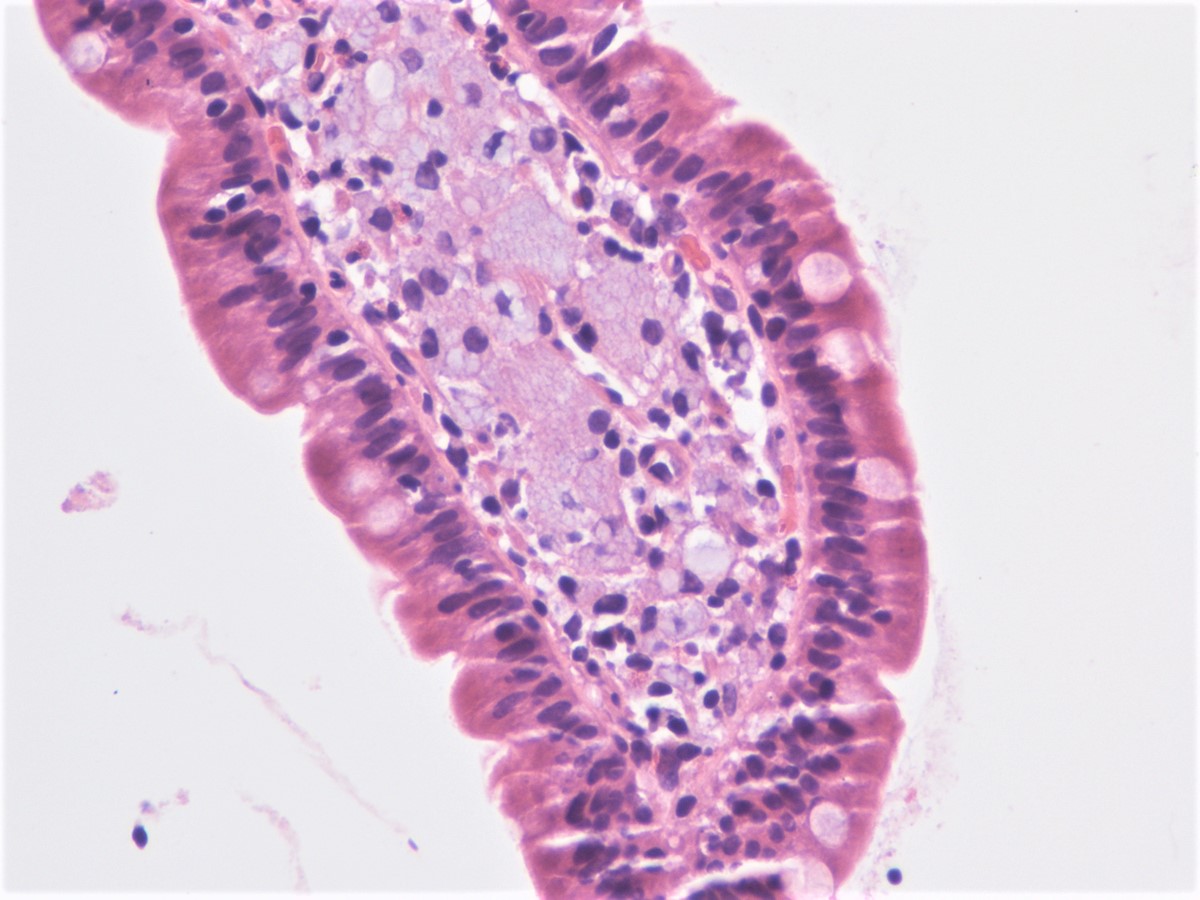

Фотографии медицинских исследований инсулиномы и синдрома Триады Уиппла